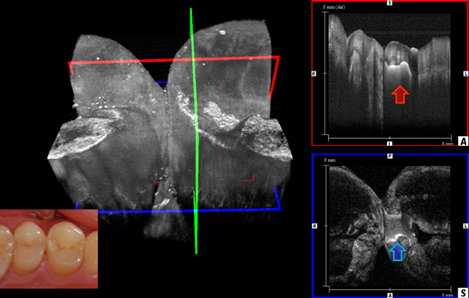

① 光干渉断層計(OCT)を応用した非侵襲的診断技術

OCTを用いてエナメル質や象牙質に生じた初期う蝕病変を非侵襲的に評価し、進行度や治療適応を的確に判断する方法を検討している。

クラウンやコンポジット修復の辺縁適合をOCTで観察し、臨床的に破壊を伴わずに界面を可視化・定量化する手法を確立している。

接着修復後に生じる微細な隙間や亀裂をOCTで可視化し、接着耐久性や修復物の信頼性を評価する新しい診断法を開発している。

① 3D波長走査型光干渉断層計を使用した研究

光干渉断層計(OCT)は近赤外光を用い、生体の断層画像を非侵襲的に得ることができます。中でも波長走査型OCT(SS-OCT)は画像深度が深く、画像処理速度も速いことから、う蝕の診断や修復物の適合性の評価など、保存修復領域における有用性が高いと考えられます。

1.接着修復窩縁部に生じたエナメル質亀裂の評価

接着修復の際、窩縁部のエナメル質には応力が集中し亀裂が生じることがある。これらの亀裂は従来の観察方法では検出が困難であったため、SS-OCTを用いて三次元的に評価した。光干渉断層像により窩縁部に生じた微細な亀裂を非侵襲的に可視化することが可能となり、接着修復の信頼性評価に新しい手法を提供すると考えられる。

2.実臨床における咬合面齲蝕の診断

咬合面の初期齲蝕は、視診やX線診査のみでは検出が難しいことが多い。そこで、実際の臨床現場においてSS-OCTを用い、咬合面齲蝕を非侵襲的に診断する方法を検討した。断層画像による光学的評価により、う蝕の進展状態を客観的に可視化することが可能となり、臨床における診断精度の向上に寄与すると考えられる。

3.OCTを用いた化学重合型1-SEAの接着評価

SS-OCTは接着材料のギャップ形成などを非破壊かつリアルタイムで観察することが可能です。化学重合型の1ステップボンディング材はその接着性能に懐疑的な意見が多かったが、本研究では接着性能もギャップ形成において、光重合型1ステップボンディング材と比較・検討を行った。